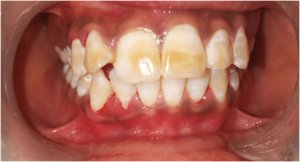

Department deals with all the treatments of teeth which alleviate pain due to pulp diseases and provide immediate solace to the patient. It also deals with the esthetic rehabilitation of the discolored, broken, mutilated teeth. Advanced endodontic treatment including micro-endodontics and regenerative therapy are also performed. Our department aims at creating and achieving excellence in the field of research and scientific development.

TREATMENTS

SERVICES